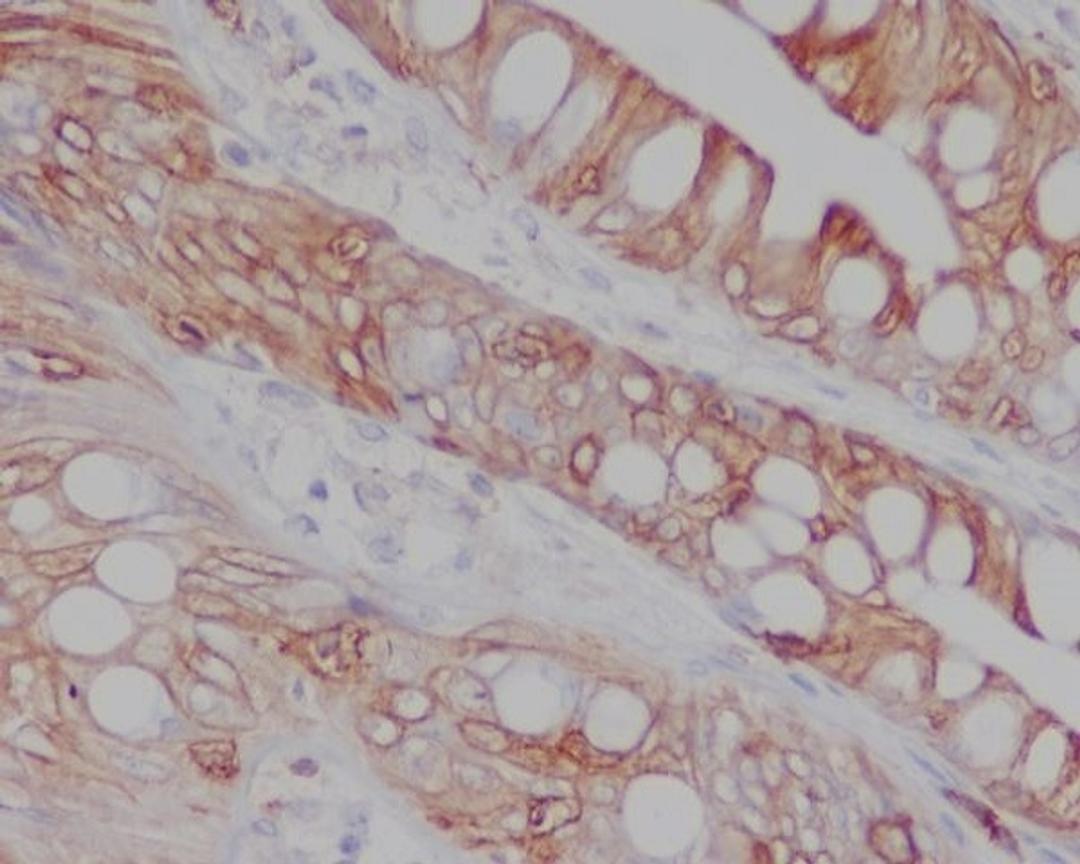

Boster Bio Anti-CD8 CD8A Rabbit Monoclonal Antibody catalog # M02236-1. Tested in IF, IHC, ICC, WB applications. This antibody reacts with Human.